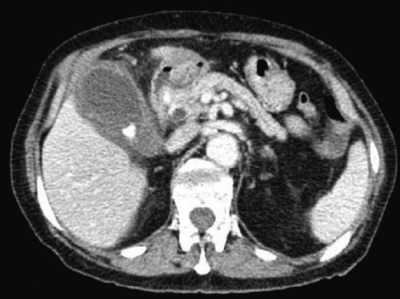

血液所見:赤血球 433 万、Hb 14.0 g/dL、Ht 42 %、白血球 12,400、血小板 17 万。血液生化学所見:アルブミン 4.5 g/dL、AST 24 U/L、 ALT 18 U/L、LD 161 U/L(基準 176〜353)、ALP 350 U/L(基準 115〜359)、γ-GTP 94 U/L(基準8〜50)、尿素窒素 21 mg/dL、クレアチニン0.7 mg/dL。 CRP 13 mg/dL。腹部造影CTを示す。